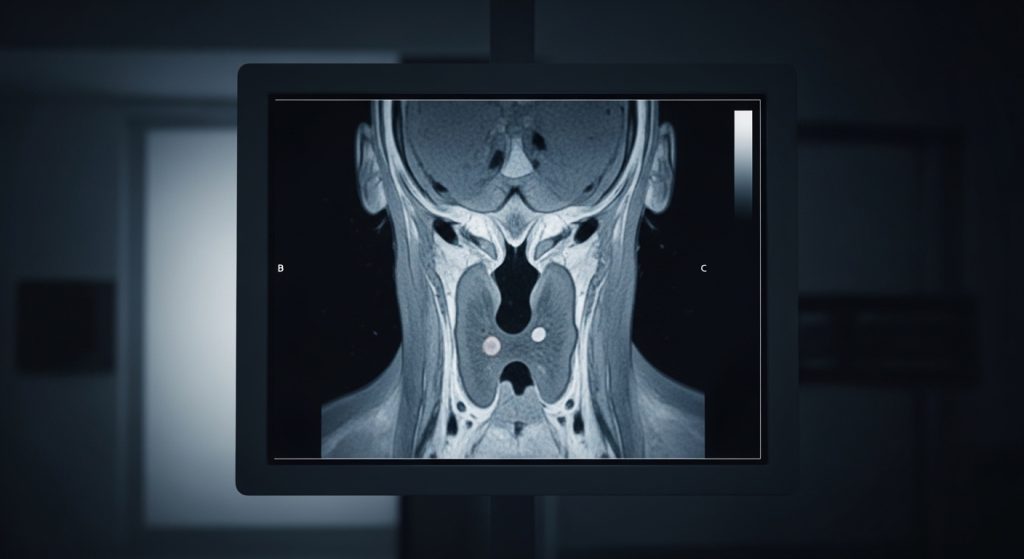

- Imaging, often a high-resolution CT (HRCT) scan to look for scarring patterns

Because patterns can overlap with other lung diseases, some people benefit from a multidisciplinary review (pulmonology, radiology, pathology).